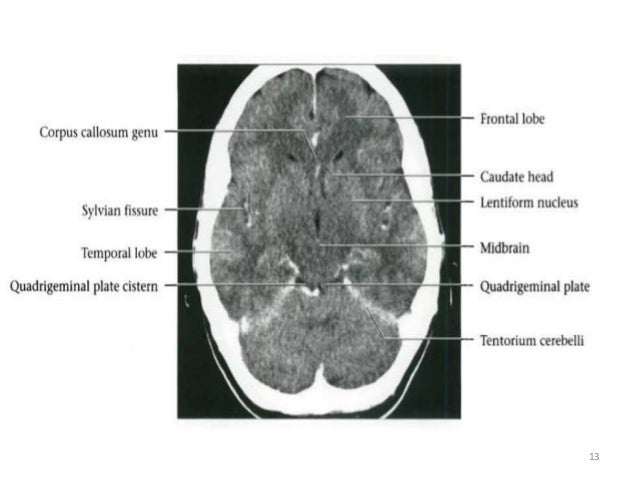

Magnetic Resonance Images Of The Brain Mri Brain Sagittal T2 Weighted Sequence Stock Photo Image Of Magnetic Weighted 191225152 from thumbs.dreamstime.com Anatomy of brain by mri sagittal images fig. Basic radiological anatomy of the brain and spine with annotated ct and mri images covering the brain, including the brainstem structures and ventricles, and whole spine. The central nervous system (defined as the brain and spinal cord) is usually considered to have seven basic parts: